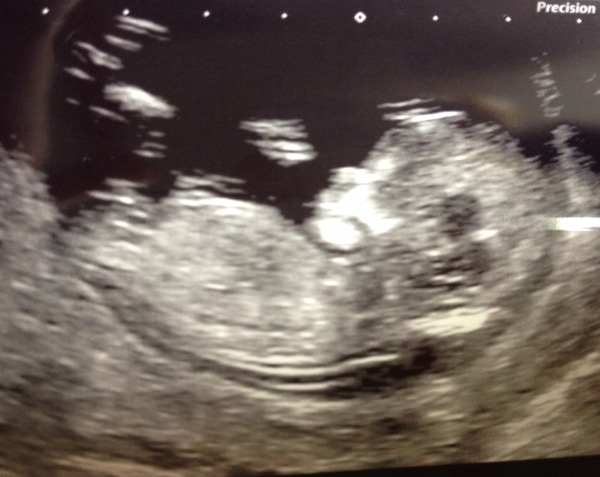

Lovely pictures ladies!

14 & 3 today